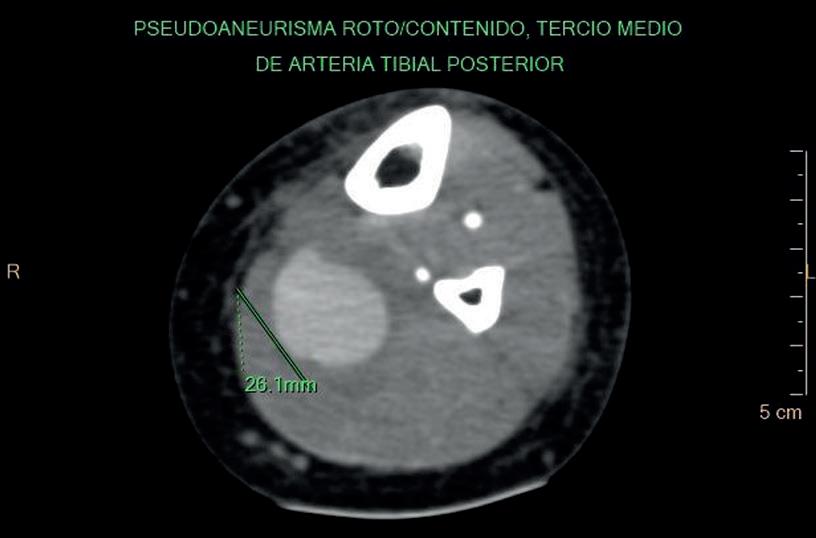

Figura 1 Anatomía de un vaso sanguíneo arterial. Figura 2 Características diferenciales de los aneurismas, pseudoaneurismas . Figura 3 Dilatación vascular con un diámetro de 17 mm x 24 mm a nivel del tercio medio, de la cara posterior de la pierna izquierda evidenciando el signo Yin-Yang en su interior el cual representa la lesión de la pared vascular con una colección extraluminal de sangre conectada con el vaso principal, característico del estudio Doppler, el cual demuestra una curva con flujo anterógrado y retrógado a nivel del pseudoaneurisma. Figura 4 Corte axial de estudio tomográfico con contraste endovenoso de la pierna izquierda el cual demuestra dilatación de la arteria tibial posterior a nivel del tercio medio. (pseudo aneurisma roto y contenido).

Evidenciando irregularidad parietal y tortuosidad de la arteria tibial posterior izquierda a nivel del tercio medio. Asociada a dilatación sacular y otro de similares características inferior a la descripta. Esta última poco delimitada, de pared irregular con un diámetro de 26 mm. (Figuras 4, 5, 6 y 7). Asociado a alteración de los planos musculares adyacentes y del tejido subcutáneo en toda la extensión de la pierna. Por sus características fue interpretado como pseudoaneurisma roto y contenido.